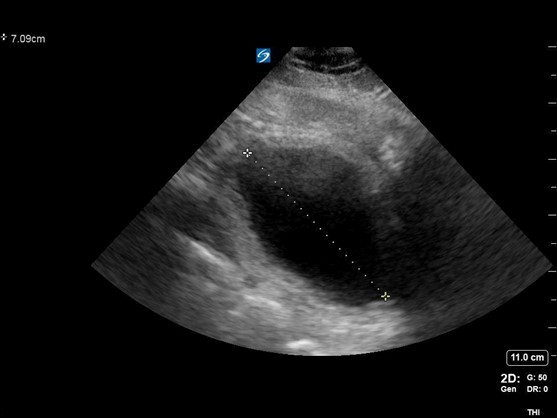

A 65-year-old male with a history of HTN, BPH, IDDM, and lumbar spinal stenosis presented to the ED with low back pain and lower extremity weakness. He denied fever, abdominal pain, and dysuria. He reports that he is able to urinate but unable to state if his urinary frequency has increased beyond “my normal prostate issues.” He notes he has fallen twice because “my legs just seem to give out on me.” On physical exam, he demonstrates 4+/5 bilateral LE strength, mild distal sensory loss, and absent patellar and Achilles reflexes. His rectal tone was equivocal. After use of a urinal, bedside POCUS was used to measure his post-void residual bladder volume:

Figure 2. A sagittal view of the bladder with cranial-caudal measurement

Figure 3. Calculation of bladder volume using the ellipsoid method (L x W x H x 0.52 = mL)

Findings concerning for Cauda Equina were all present in this patient’s history, physical exam, and workup. Current literature defines normal post-void bladder volume in adults as < 50 mL in patients under 65 years of age, and < 100 mL in those older than 65. Two hundred milliliters or greater is generally regarded as the threshold for retention.1 In this case, the patient was just on the cusp of normal vs abnormal post-void urinary volume, but with his other clinical signs and symptoms, warranted emergency spine consultation and MRI. Imaging eventually showed severe compression of the spinal nerve roots by discs at the L2-3 and 3-4 levels, necessitating emergent decompression.

With the patient in supine position, a 2- to 5-MHz curvilinear probe is placed above the patient’s symphysis pubis in the midline position. To obtain a cross-sectional view of the bladder, the probe is oriented with the marker towards the patient’s right side. Once an image is obtained, the probe can be rotated 90 degrees to orient the marker towards the patient’s head for a long or sagittal view of the bladder. Bladder volume is obtained using the ellipsoid formula of depth x width x height x 0.52 (correction factor). Normal bladder findings include a smooth wall measuring 3-5 mm, which may decrease to 2-3 mm when filled. As discussed above, normal post-void residual volume in patients < 65 yo is < 50 mL and < 100 mL in those over the age of 65. A post-void residual of > 100 should raise suspicion about a mechanical, pharmaceutical, or neurogenic cause of retention.2-7